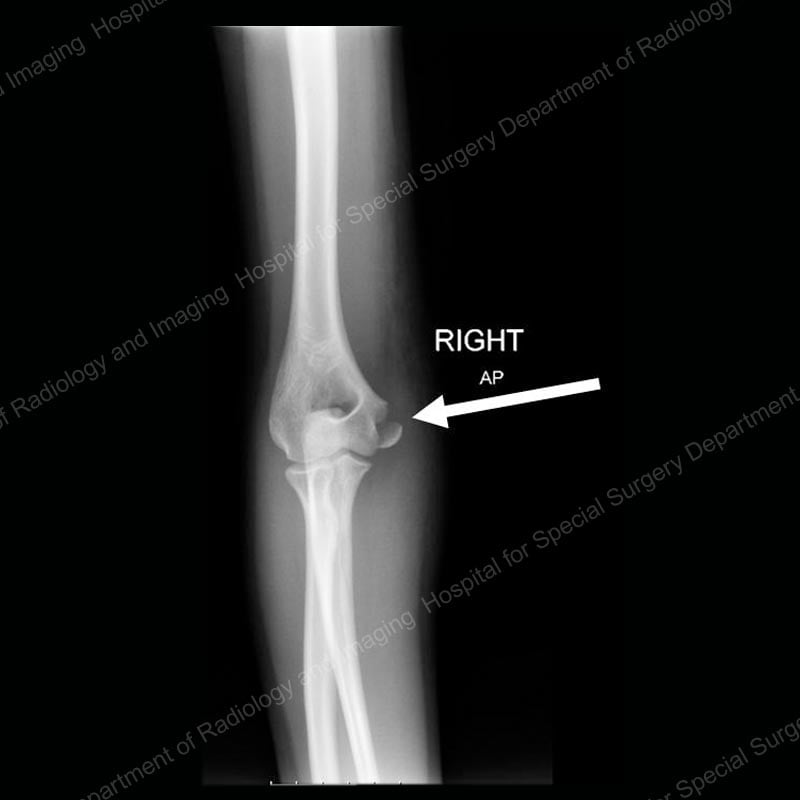

Figure 3: Anterior (front) X-ray view of a lateral condyle fracture prior to treatment. The arrow points to the fracture line.

Figure 4: Lateral (side) X-ray view of a lateral condyle fracture prior to treatment. The arrow points to the fracture line.

Orthopedic surgeons classify these injuries based on the degree to which they are displaced and determine treatment accordingly. If the fracture is non-displaced, that is, the fracture line can be seen on an image, but the bone has not shifted out of position, the patient may only require immobilization of the arm in a splint or cast. However, if any displacement is found, the bone needs to be realigned and stabilized with pins or wires as in supracondylar fractures. (Please see Figure 2 for an example of this type of wiring.) This surgery may or may not require an incision, depending on the extent of the displacement.